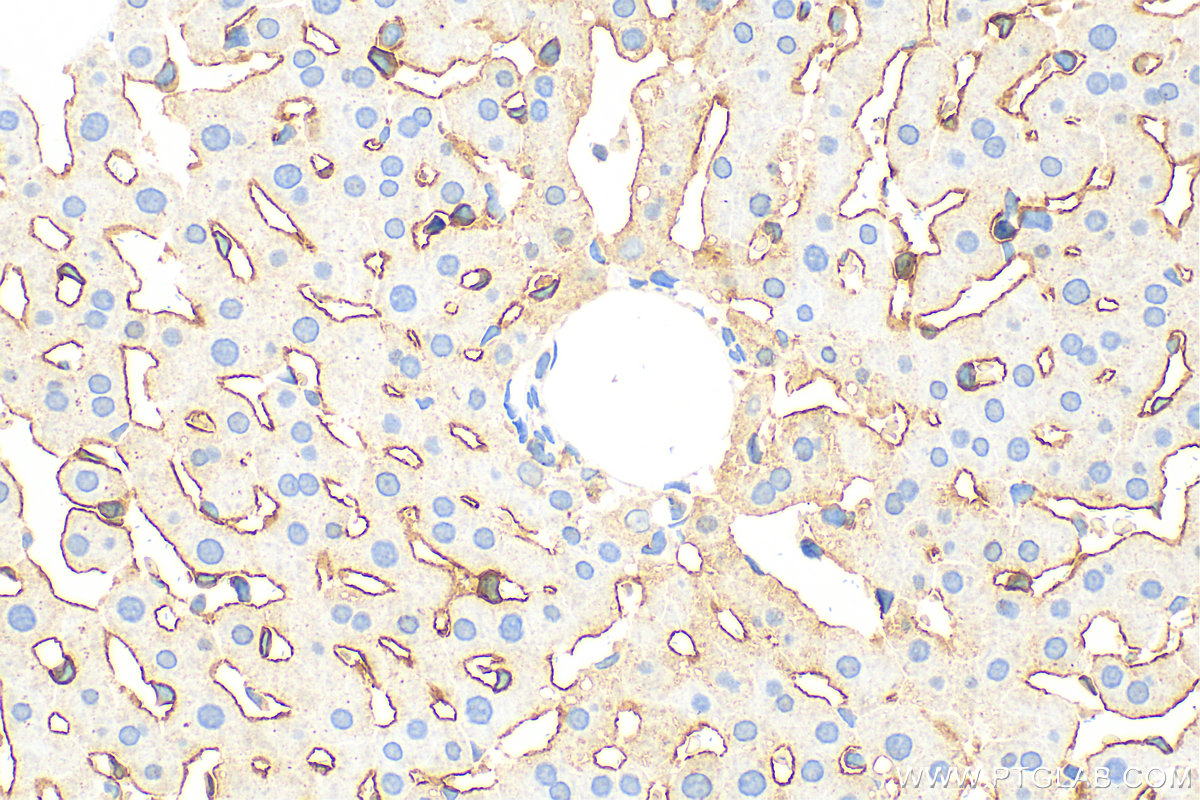

Validation Data Gallery View All